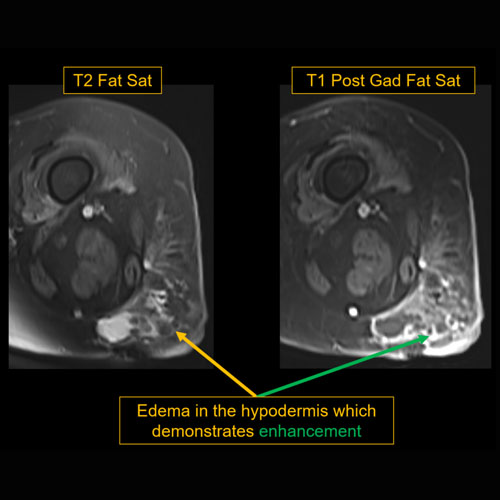

There is edema or hyperenhancement. |

Yes | NA |